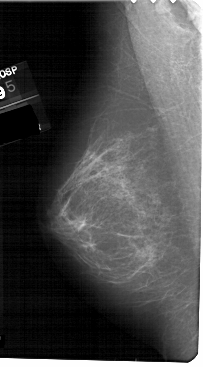

A_1487_1.LEFT_MLO

ics_version 1.0

filename A-1487-1

DATE_OF_STUDY 5 10 1995

PATIENT_AGE 36

FILM_TYPE REGULAR

DENSITY 2

DATE_DIGITIZED 2 11 1998

DIGITIZER HOWTEK 43.5

LEFT_MLO LINES 5491 PIXELS_PER_LINE 3031 BITS_PER_PIXEL 12 RESOLUTION 43.5 NON_OVERLAY